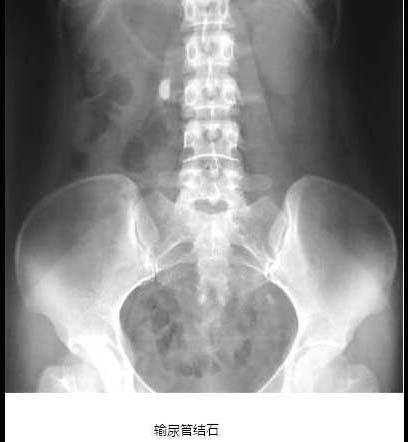

问题 关于输尿管结石,下列哪项是错误的 ( )

选项 A、一侧输尿管结石、对侧肾结石,应先处理对肾功能影响较大的肾结石 B、结石常停留或嵌顿于肾盂输尿管连接处、输尿管跨越髂血管处及输尿管膀胱连接处 C、输尿管结石多继发于肾结石 D、结石位于输尿管下1/3处最为多见 E、结石以上输尿管部分常有扩张